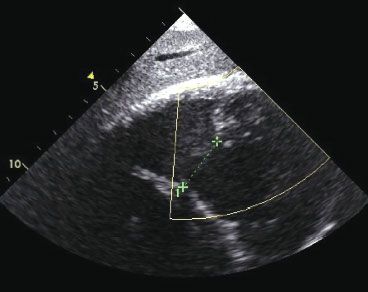

Twelve hours after admission, the patient had hypotension, atrial fibrillation, and worsening respiratory distress. ST-segment elevation also developed in the inferior leads on a 12-lead ECG. A repeated 2-dimensional transthoracic echocardiogram showed inferior wall hypokinesis, along with a ventricular septal defect (VSD) in the inferoseptum (shown here). Within 24 hours of admission, the patient sustained a cardiac arrest. Efforts to resuscitate her were unsuccessful.

Autopsy revealed inflammation of the myopericardium, normal coronary arteries, and a VSD measuring 3 cm in diameter, with necrosis of the inferior wall. To our knowledge, this case of VSD as a complication of myocarditis is the first report of such an occurrence.